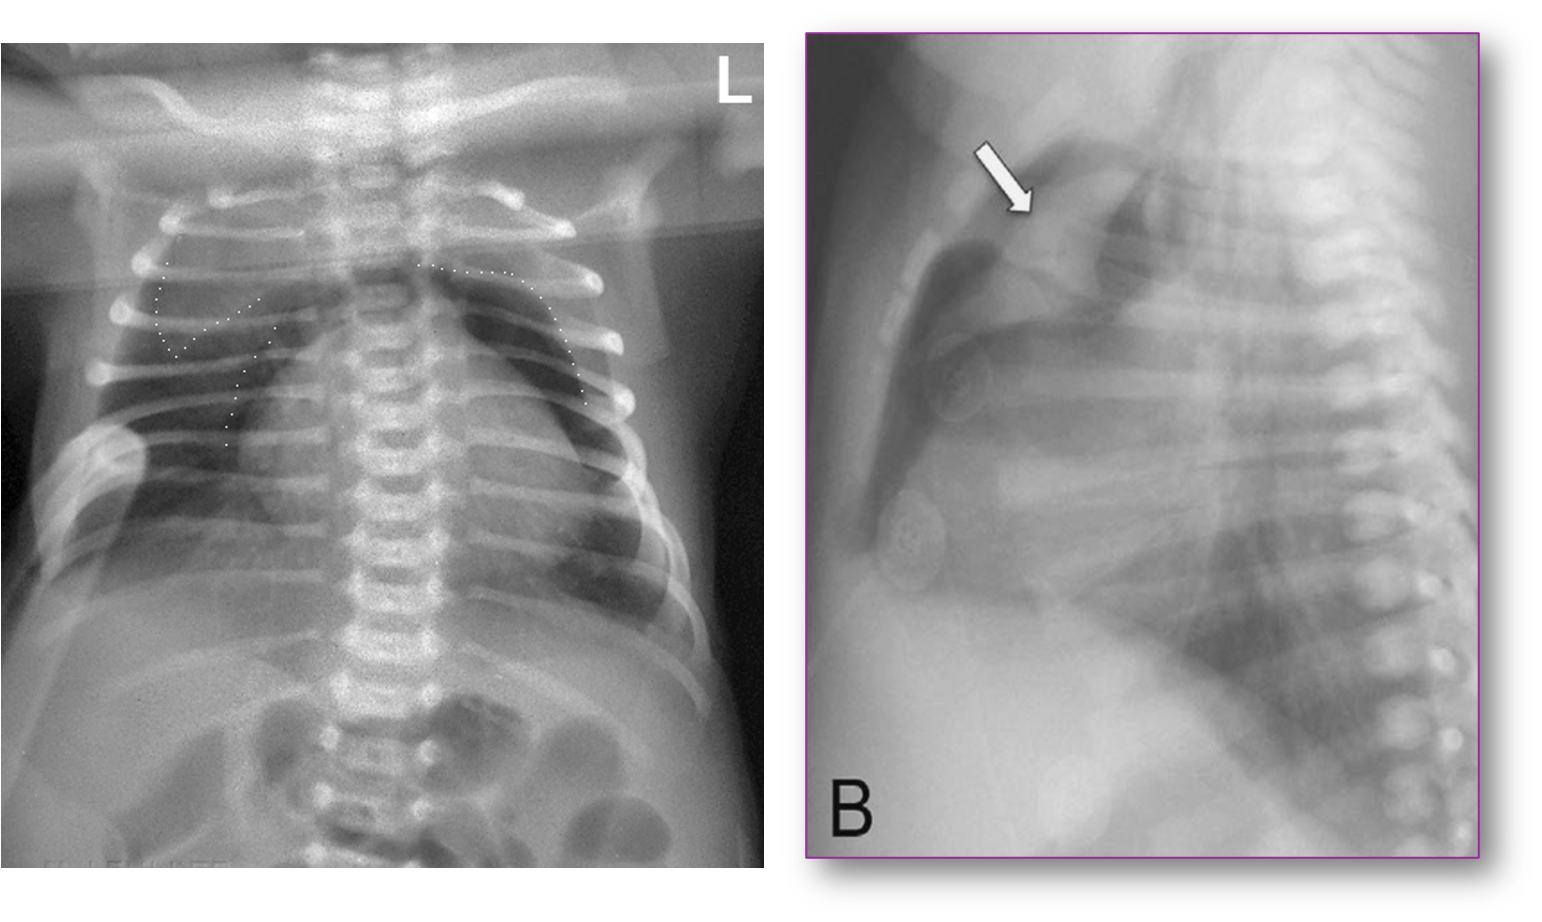

Newborn with Mild Respiratory Distress

Had pneumomediastinum elevating the thymus “spinnaker sail” sign.

Pneumopericardium

With air completely surrounding the heart, demarcating the pericardial sac.